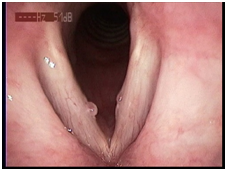

1、 动态喉镜:可在高清模式下动态观察声带黏膜波振动、声门关闭等情况,该检查能精确量化声带病变的范围与程度,视频资料便于保存可用于治疗前后的疗效对比。

声带息肉术前 声带息肉术后

声带麻痹术前 声带麻痹术后